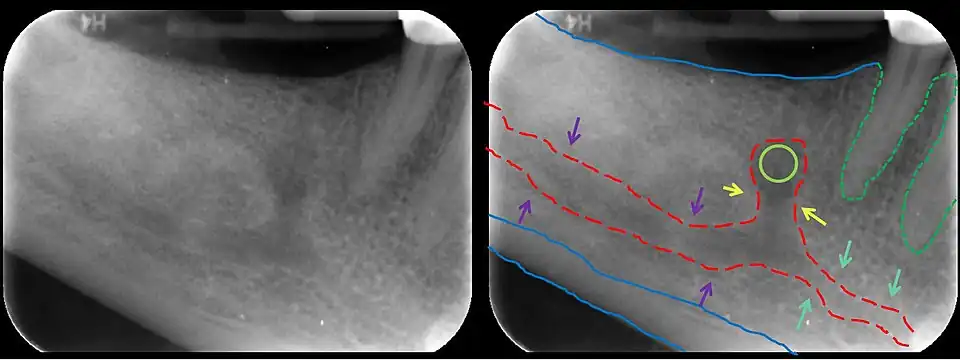

En la anatomía humana, el canal mandibular es un canal dentro de la mandíbula que contiene el nervio alveolar inferior, la arteria alveolar inferior y la vena alveolar inferior . Corre oblicuamente hacia abajo y hacia adelante en la mandíbula, y luego horizontalmente hacia adelante en el cuerpo, donde está situado debajo de los alvéolos y se comunica con ellos por pequeñas aberturas.

El canal mandibular está bastante cerca de los ápices del segundo molar en el 50% de las radiografías. En el 40%, el canal está alejado de los ápices de la raíz, y en sólo el 10% de las radiografías los ápices de la raíz parecían penetrar en el canal.

En la terapia del canal radicular del segundo molar se debe tener cuidado de no extender demasiado el escariador o los materiales de relleno del canal radicular porque hay un posible riesgo de lesión del nervio alveolar inferior[2]